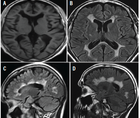

On the MRI scan, ARIA-E appears as a single area or multiple areas of T2/FLAIR hyperintense signal change of variable extent (Figure 6). The most common locations are the occipital lobes, followed by frontal, parietal, and temporal lobes, but the cerebellum may also be involved.44,46 Although typically confined to the white matter, the edema can also affect the gray matter, appearing as gyral swelling. At times, leakage of proteinaceous fluid into the leptomeningeal/subpial space causes sulcal FLAIR hyperintensity (Figure 7), which resembles focal subarachnoid hemorrhage.44,46 In these cases, however, susceptibility-weighted imaging does not reveal the presence of blood products.44 ARIA-E does not cause restricted diffusion, which helps differentiate it from acute ischemia.46

Figure 6. Amyloid-related imaging abnormalities, both with edema and microhemorrhages, after the 5th infusion of antiamyloid therapy. On the initial scan, there is radiographically mild vasogenic edema in the right frontal lobe (A). On the follow-up scan 3 months later, the edema has resolved (B). Intermixed with the edema, on the initial scan, radiographically severe microhemorrhages are present: their number, including adjacent slices, exceeds 10 (C). On the 3-month follow-up scan, the microhemorrhages are stable (D).

ARIA-H can present with various imaging manifestations. Most commonly, microhemorrhages occur, often colocalizing with ARIA-E (Figure 6). Superficial siderosis is a less common finding (Figure 8). Rarely, larger intracerebral hemorrhages (>1 cm) have been reported.48